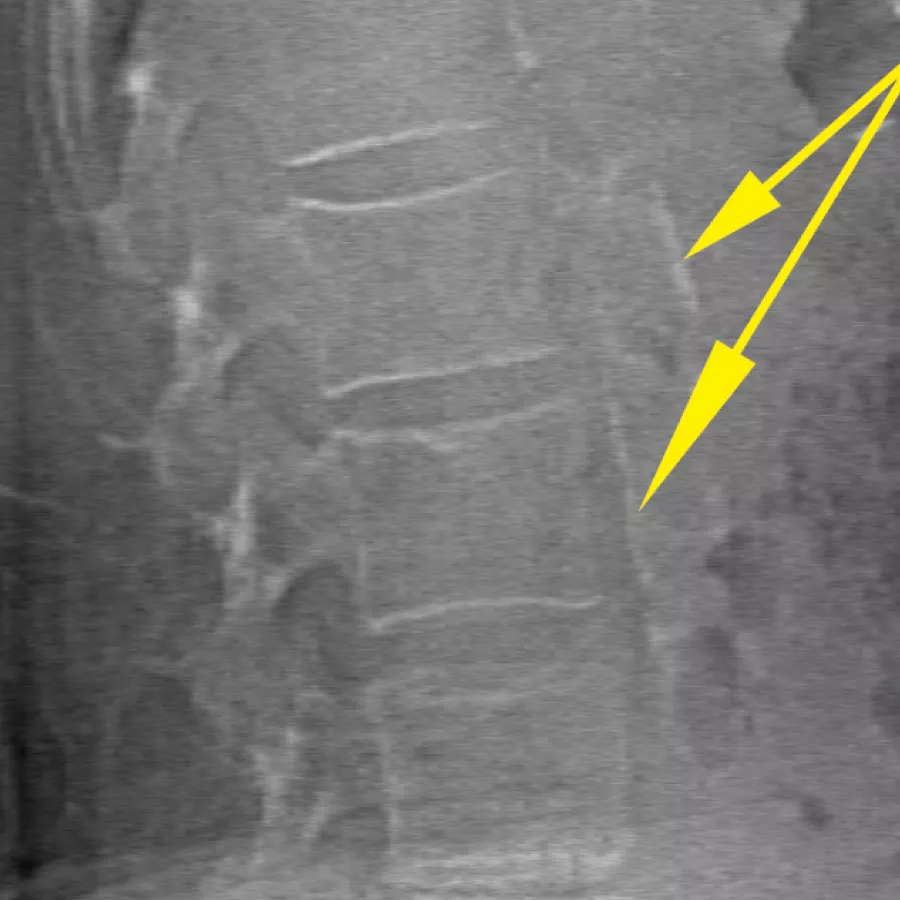

Assess fracture risk by combining an accurate measurement of bone density with high-resolution vertebral imaging. You can identify spine fractures with a low-dose, single-energy image in 10 seconds.

Improve accuracy and reduce post-exam analysis errors with precise, software-assisted placement of inter-vertebral disc spaces for graphic analysis.